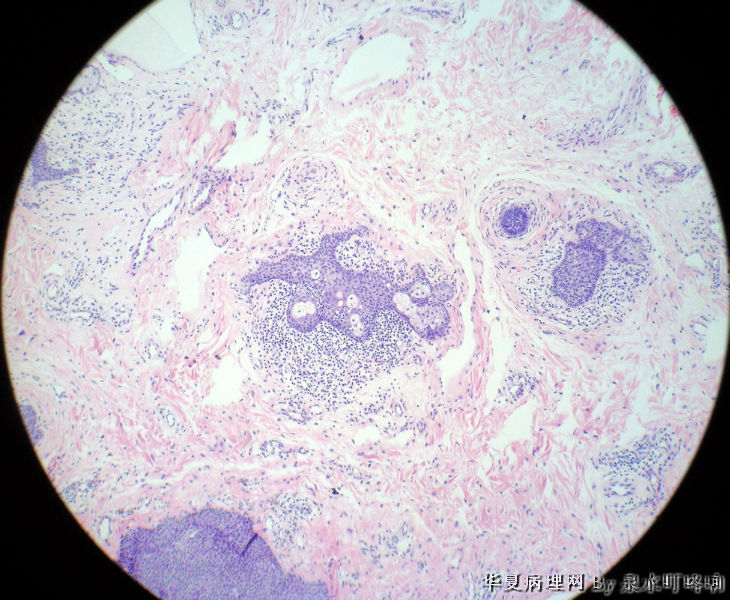

左耳后肿物

男,80岁,左耳后肿物十余年。左耳后肿物图1

棘层肥厚型脂溢性角化症

脂溢性角化病

同意脂溢性角化病,该例主要需要和汗孔瘤鉴别。

毛发上皮瘤

典型的棘层肥厚型脂溢性角化症!